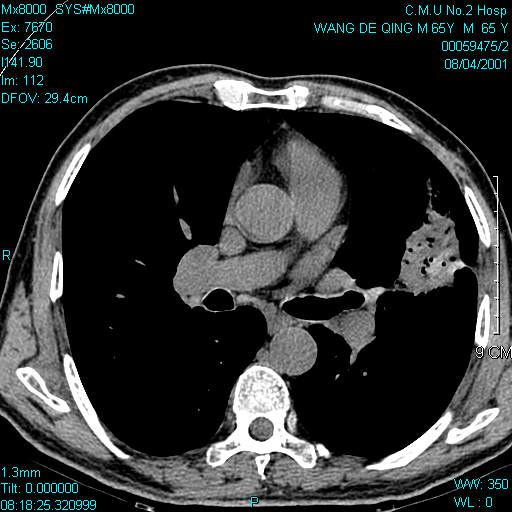

男,65

首选考虑左上肺舌段慢性炎性肿块,依据:周边肺野欠清,病灶与胸膜牵扯太多,周边见多发细支气管扩张,局部可见纤维条块及瘢痕旁气肿,左肺门不大。但还是要与肺癌区别。

首先考虑炎性肿块,依据:病灶大体呈梭形,虽有长短不一的毛刺,但边缘大部较清晰,且毛刺多较长,不是那种细密毛刺,并有索条影与肺门及邻近胸膜粘连,肺门和纵隔内未见明显肿大淋巴结。

但考虑到病人年龄、发病率及没有明显慢性炎症史,不完全排除周围型肺癌。